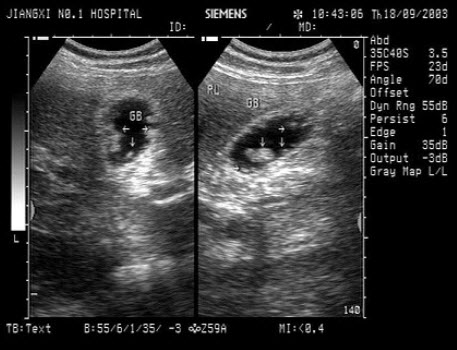

17、单项选择题

男,64岁,右上腹反复疼痛不适数10年,加重5天。声像图如图所示,诊断为()

A.肝内钙化带

B.胆囊充满型结石并萎缩性胆囊炎

C.胆囊蛔虫

D.肠襻回声

E.胆囊癌